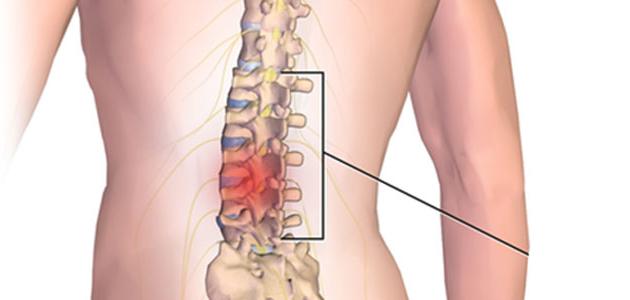

ما هي مخاطر عمليات العمود الفقري وكيف تتجنبها ؟

يجب على المريض معرفة مخاطر عمليات العمود الفقري قبل الإقدام على أي خطوة، فعمليات العمود الفقري حساسة ودقيقة للغاية والتي قد ينتج عنها مضاعفات المريض في غنى عنها. وفي هذه السطور سنتناول كل ما يخص عمليات العمود الفقري وبعض المخاطر الناجمة عن هذا النوع من الجراحات أو طرق العلاج.

علاج الديسك الضاغط على العصب

أو ما يسمى بالانزلاق الغضروفي Herniated disk، والذي يحدث بسبب انتفاخ في المادة الرخوة الداخلية في القرص الصلب وخروجها خارج العمود الفقري وضغطها على أحد الأعصاب التي تخرج من الحبل الشوكي مما يسبب للمريض عدد من الأعراض مثل: الألم في الظهر أو في القدم أو في اليد وخدران وتنميل وضعف بالعضلات، ومن العوامل التي تزيد من نسبة الإصابة بمرض الديسك الضاغط على العصب هي: الوزن الزائد والعوامل الوراثية وأخيرًا الوظيفة كأن تتطلب الوظيفة الكثير من الحمل والدفع والسحب، يقوم الطبيب بتشخيص الديسك الضاغط على العصب عن طريق الفحص السريري ثم القيام ببعض صور الأشعة الأخرى لمعرفة موقع القرص المتضرر، ثم يقوم الطبيب بإعطاء علاج الديسك المناسب.